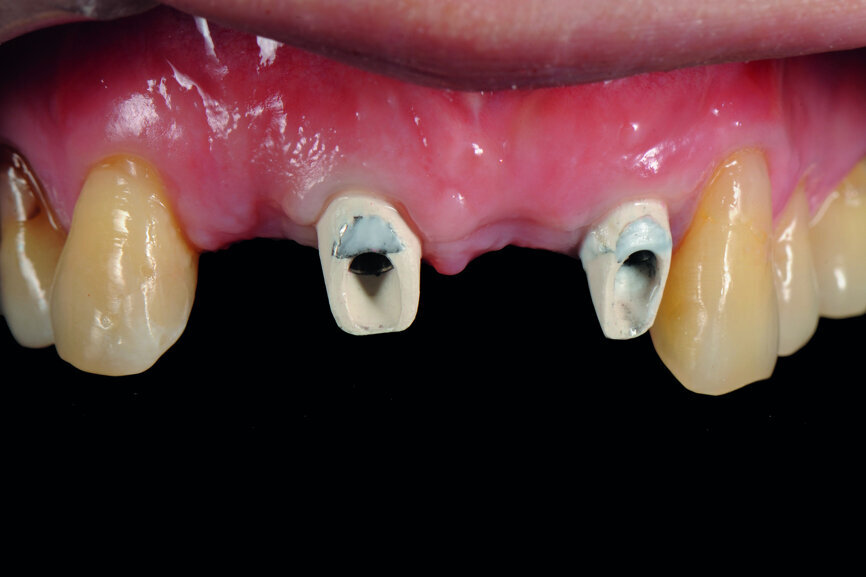

A 40-year-old female patient had sustained trauma to her anterior teeth caused by accidental syncope three weeks before. The clinical examination found that tooth #11 had been luxated; the crowns of teeth #12 and 21 had fractured, with the residual margin extending 3–5 mm below the gingiva and the teeth affected by Grade III mobility; and the crown of tooth #22 had fractured, with the residual margin at gingival level. There were no obvious abnormalities in the remaining teeth (Figs. 1–4). After excluding major systemic diseases, it was decided that she required fixed implant restoration with high demands regarding aesthetics and function.

Fig. 1: Pre-op frontal view of the anterior teeth.

Fig. 15: Insertion of provisional abutments.